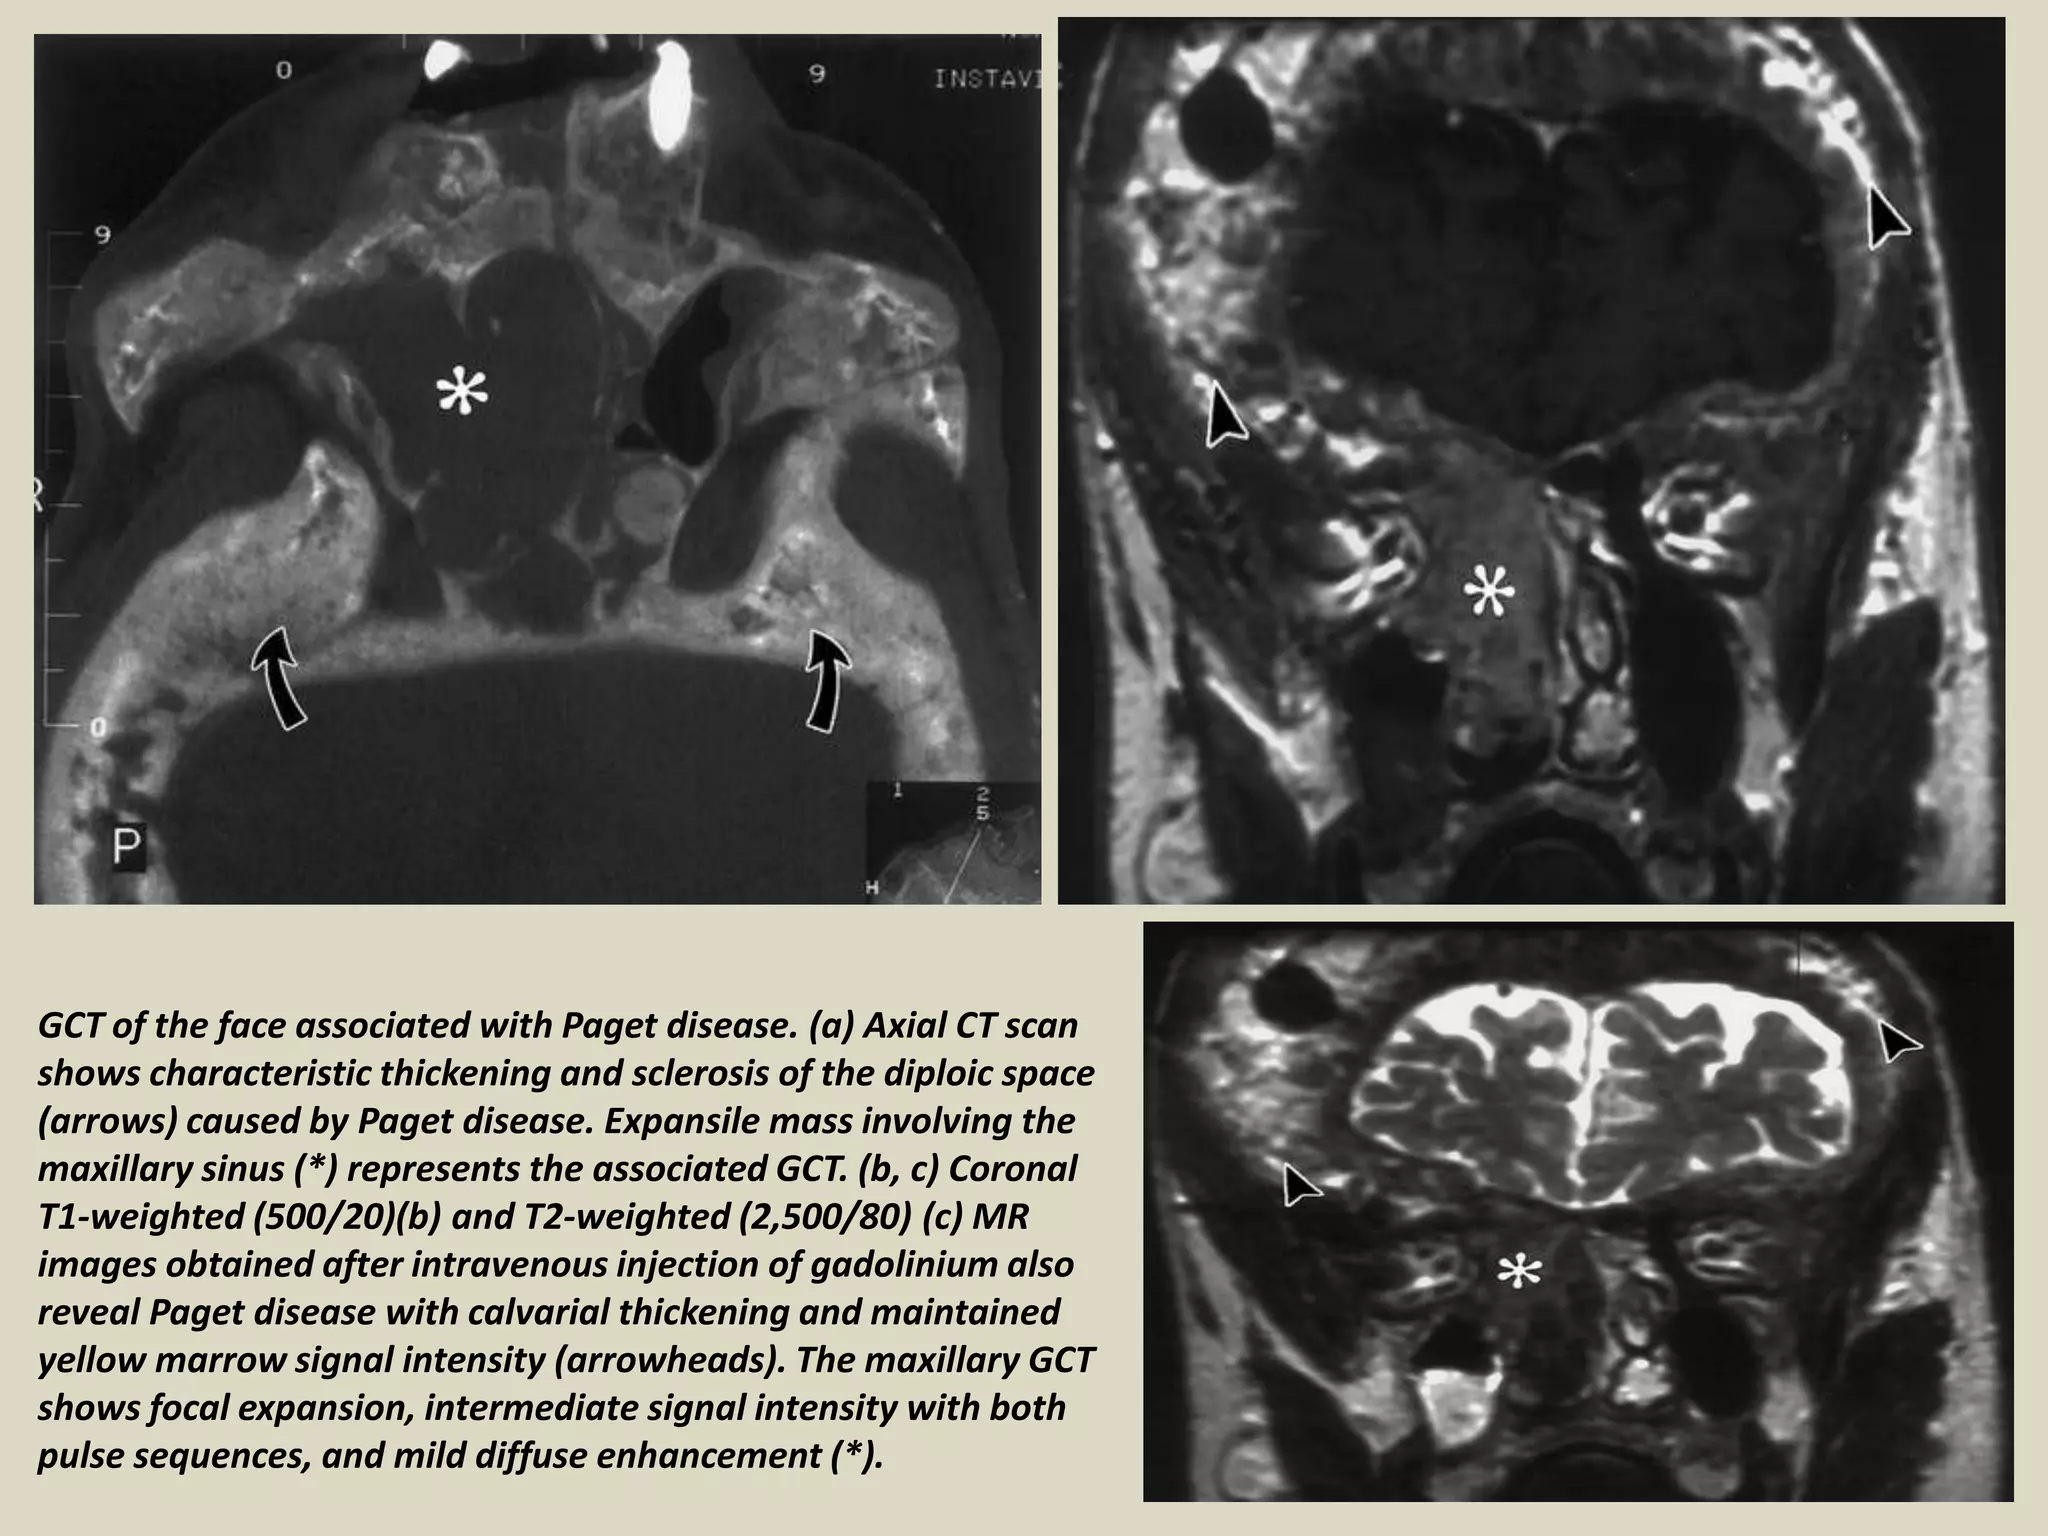

GCT of the face associated with Paget disease. (a) Axial CT scan

shows characteristic thickening and sclerosis of the diploic space

(arrows) caused by Paget disease. Expansile mass involving the

maxillary sinus (*) represents the associated GCT. (b, c) Coronal

T1-weighted (500/20)(b) and T2-weighted (2,500/80) (c) MR

images obtained after intravenous injection of gadolinium also

reveal Paget disease with calvarial thickening and maintained

yellow marrow signal intensity (arrowheads). The maxillary GCT

shows focal expansion, intermediate signal intensity with both

pulse sequences, and mild diffuse enhancement (*).

GCT of theface associated with Paget disease. (a) Axial CT scan shows characteristic thickening and sclerosis of the diploic space (arrows) caused by Paget disease. Expansile mass involving the maxillary sinus (*) represents the associated GCT. (b, c) Coronal T1-weighted (500/20)(b) and T2-weighted (2,500/80) (c) MR images obtained after intravenous injection of gadolinium also reveal Paget disease with calvarial thickening and maintained yellow marrow signal intensity (arrowheads). The maxillary GCT shows focal expansion, intermediate signal intensity with both pulse sequences, and mild diffuse enhancement (*).